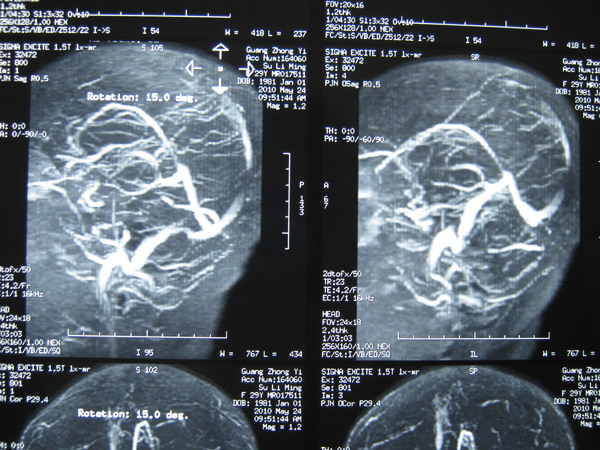

2011年5月1日,覃某顺产1名女婴后出现发作性意识障碍,伴双目上视,伴牙关紧闭、口吐白沫、四肢抽搐、二便失禁,醒后伴头晕、四肢乏力、左侧肢体麻木等不适症状,遂到当地医院就诊。在其住院过程中出现意识障碍伴左侧肢体活动障碍、左下肢肿胀等症状,在进行头颅MRI+MRA等检查后,覃某被当地医院诊断为“颅内静脉窦血栓形成并伴脑皮质出血、症状性癫痫、左下肢静脉血栓形成”。

上矢状窦血栓形成1

上矢状窦血栓形成2